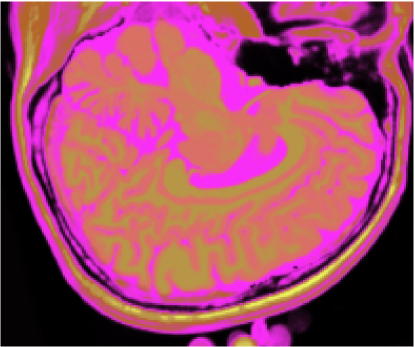

3.1 Classificadores Dialéticos Objetivos

A figura 6 mostra os resultados de classificação, enquanto a figura 7 exibe os resultados de quantização para a imagem sem ruído da fatia 97, figura 5, usando os métodos KO, CM, KM, ODC-PME e ODC-CAN. Esses resultados ilustram qualitativamente as diferenças entre os métodos de classificação e quantização, dado que a fatia 97 possui todas as 13 classes presentes na análise [51].

Figura 6: Composição colorida R0-G1-B2 das imagens da fatia 97 ponderadas em PD, T1subscript𝑇1T_{1} e T2subscript𝑇2T_{2} (a) e resultados de classificação usando os métodos KO (b), CM (c), KM (d), ODC-PME (e) e ODC-CAN (f)

A tabela 2 mostra os resultados da avaliação dos métodos de classificação não supervisionada quanto à quantização vetorial, usando os índices de fidelidade ϵMEsubscriptitalic-ϵME\epsilon_{\textnormal{ME}}, ϵMAEsubscriptitalic-ϵMAE\epsilon_{\textnormal{MAE}}, ϵMSEsubscriptitalic-ϵMSE\epsilon_{\textnormal{MSE}}, ϵRMSEsubscriptitalic-ϵRMSE\epsilon_{\textnormal{RMSE}} e ϵPSNRsubscriptitalic-ϵPSNR\epsilon_{\textnormal{PSNR}}, considerando todas as 181 fatias com 3 bandas (DP, T1subscript𝑇1T_{1} and T2subscript𝑇2T_{2}), para os métodos KO, CM, KM, ODC-PME e ODC-CAN e 0% de ruído. Já os gráficos das figuras 8, 9, 10 e 11 mostram os resultados em função do nível percentual de ruído para os diversos métodos, para um total de 6 volumes de 181 fatias de 3 bandas, totalizando 1086 imagens coloridas, ou 3258 imagens em níveis de cinza.

Figura 7: Composição colorida R0-G1-B2 das imagens da fatia 97 ponderadas em PD, T1subscript𝑇1T_{1} e T2subscript𝑇2T_{2} (a) e resultados de quantização usando os métodos KO (b), CM (c), KM (d), ODC-PME (e) e ODC-CAN (f)

Os gráficos das figuras 14, 15, 16 e 17 mostram os resultados das medidas dos índices de fidelidade ϵMEsubscriptitalic-ϵME\epsilon_{\textnormal{ME}}, ϵMAEsubscriptitalic-ϵMAE\epsilon_{\textnormal{MAE}}, ϵRMSEsubscriptitalic-ϵRMSE\epsilon_{\textnormal{RMSE}} e ϵPSNRsubscriptitalic-ϵPSNR\epsilon_{\textnormal{PSNR}}, enquanto os gráficos das figuras 18 e 19 exibem os resultados do erro de quantização, Jesubscript𝐽𝑒J_{e}, e do índice de Omran, Josubscript𝐽𝑜J_{o}, para os métodos KO, CM, KM, IC-CAN, EQ-CAN, IC-PME e EQ-PME, em função dos níveis percentuais de ruído, para os 6 volumes de 181 fatias de 3 bandas. A figura 20 mostra os resultados de classificação, enquanto a figura 21 exibe os resultados de quantização para a imagem sem ruído da fatia 97, figura 5, usando os métodos IC-CAN-KM, IC-PME-KM, EQ-CAN-KM e EQ-PME-KM. É possível perceber a partir das imagens que a introdução da otimização dialética permitiu ao k-médias identificar diferentes classes dentro do fundo da imagem.